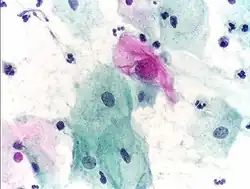

Cytopathology: microscopic appearance of a Pap test. The pink cell at the center with a large nucleus is abnormal, compatible with low-grade dysplasia.

• Cytopathology – the examination of loose cells spread and stained on glass slides using cytology techniques

Cytopathology is a sub-discipline of anatomical pathology concerned with the microscopic examination of whole, individual cells obtained from exfoliation or fine-needle aspirates. Cytopathologists are trained to perform fine-needle aspirates of superficially located organs, masses, or cysts and are often able to render an immediate diagnosis in the presence of the patient and consulting physician. In the case of screening tests such as the Papanicolaou smear, non-physician cytotechnologists are often employed to perform initial reviews, with only positive or uncertain cases examined by the pathologist. Cytopathology is a board-certifiable subspecialty in the U.S.